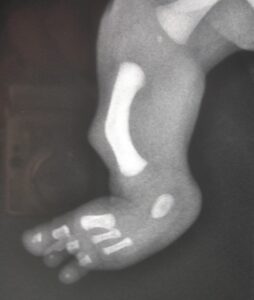

Foot deformity

In fibular hemimelia, the foot can be affected to varying degrees. The lateral aspect of the foot is usually primarily affected, precisely because the initial pathological process (during pregnancy) affects the lateral development of the leg (fibula) and foot.

This frequently results in the absence of the toes and lateral metatarsals, to varying degrees (four-toed foot, three-toed foot, etc.).

This is associated with numerous other possible malformations, which can significantly affect the position of the foot.